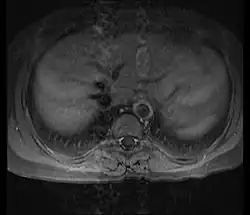

Imaging studies

Non-invasive imaging is critical for diagnosing and monitoring. Magnetic resonance angiography (MRA) and computed tomography angiography (CTA) are often sufficient to visualize vessel narrowing, occlusion, or aneurysm formation.[18] MRA uses radio waves and magnetic fields to produce detailed cross-sectional images of blood vessels, often enhanced with contrast agents.[19] CTA, in turn, combines X-ray imaging and computer analysis with contrast due to assess both vessel structure and blood flow.[19]

Although conventional angiography is rarely required today, it may be performed in selected cases to obtain high-resolution images. This involves inserting a catheter into a major artery or vein, injecting contrast dye, and taking X-rays to assess blood flow. Patients with Takayasu's typically exhibit multiple areas of stenosis.[19]

Ultrasound, particularly Doppler ultrasound, offers high-resolution images of superficial arteries, such as those in the neck and shoulder. It may detect early arterial wall changes before other imaging modalities can.[18]

Positron emission tomography (PET) scans, sometimes combined with CT or MRI, are useful for detecting vascular inflammation. A radiotracer is administered prior to the scan to highlight areas of reduced blood flow or increased metabolic activity, providing functional insight into disease activity.[18][19]